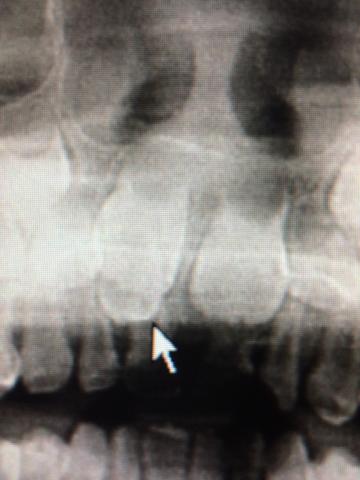

〈症例3〉下顎小臼歯部

下顎4番5番の舌側に過剰歯あり

術後写真:過剰歯抜歯したところは骨ができてきます。